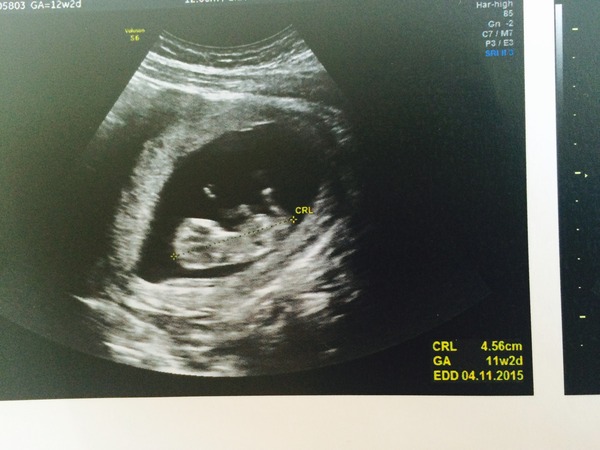

Pic from today's scan. It's not a great one because the little one was moving around like crazy! But we saw clearly two hands and two feet.

Still measuring a week behind based on LMP but I suspected I ov'd late so doctor isn't worried.

Time to tell family I think!